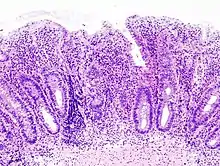

التنظير الداخلي

_endoscopic_biopsy.jpg.webp)

الأفضل في التشخيص هوَ رؤية ما يحدث داخل القولون عن طريق تنظير للقولون، أي إدخال المنظار عبر فتحة الشَرْج لرؤية بطانة الأمعاء الغليظة (القولون). والمنظار هوَ أنبوب طويل مرن مزود بضوء ومتصل بجهاز كمبيوتر وشاشة تلفزيون. ومن خلاله يرى الطبيب أي التهاب أو نزف، يجوز للطبيب أن يحد من نطاق الاختبار إذا واجه التهاب القولون الحاد؛ لتقليل خطر انثقاب القولون. وتتضمن نتائج التنظير الداخلي في التهاب القولون التقرحي ما يلي:

- فقدان مظهر الأوعية الدموية في القولون

- الحمامى (أو احمرار الغشاء المخاطي) وهشاشته

- تقرح سطحي، والذي قد يكون متكدس

- زوائد كاذبة

عادة ما يكون التهاب القولون التقرحي مستمرا من المستقيم مع إصابة المستقيم بشكل شبه كامل، بينما وجود المرض حول فتحة الشرج أمر نادر الحدوث. وتتراوح درجة التدخل بالتنظير الداخلي من التهاب المستقيم، إلى التهاب القولون من الجانب الأيسر، إلى التهاب البنكرياس، وهو التهاب يشمل القولون الصاعد.

فحص الأنسجة

يتم أخذ خزعات الغشاء المخاطي للتشخيص بشكل نهائي وتمييزه عن داء كرون، الذي تتم إدارته بشكل مختلف سريريًا. وتؤخذ العينات الميكروبيولوجية في وقت التنظير الداخلي. يتضمن المرض في التهاب القولون التقرحي عادةً تشوه بنية الخبايا والتهابها، وتكون خراجات، مع وجود نزف أو خلايا التهابية في الصفيحة المخصوصة. وفي الحالات التي تكون فيها الصورة السريرية غير واضحة، غالبا ما يلعب تحليل الأنسجة وشكلها دورًا محوريًا في تحديد التشخيص وبالتالي العلاج. وعلى النقيض من ذلك، قد يكون تحليل الخزعة غير محدد، وبالتالي فإن التقدم السريري للمرض يجب أن يحدد علاجه.